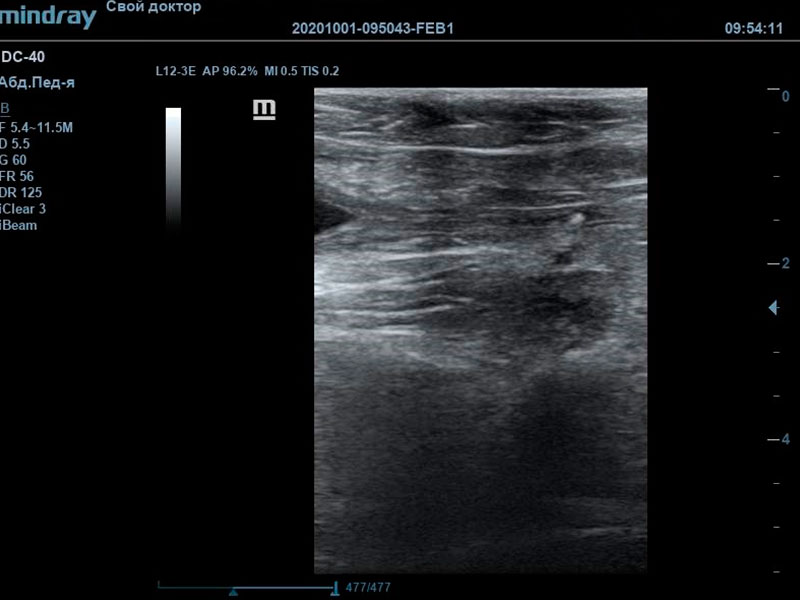

При проведении ультразвуковой диагностики врачом были выявлены крайняя степень наполнения мочевого пузыря, обильный пристеночный осадок с акустической тенью. Мочевой треугольник и проксимальная часть уретры также были расширены, в данной локации также визуализировались сформированные конкременты, размером до 3 мм. В почках определялись признаки билатеральной пиелоэктазии на фоне нарушения оттока мочи из мочевого пузыря.